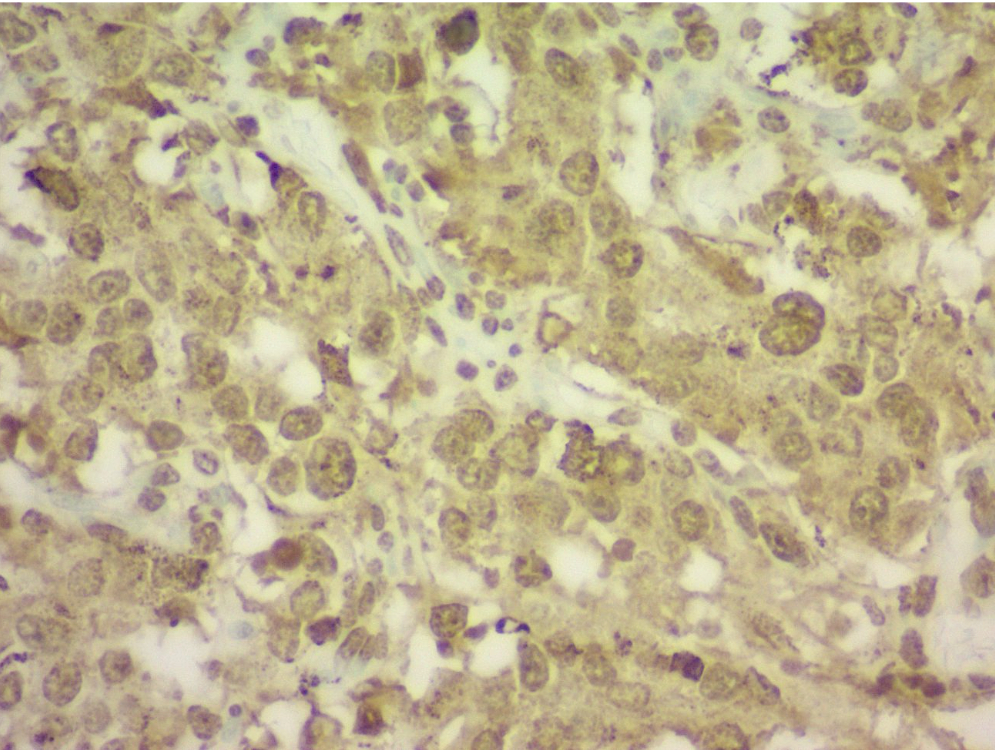

A 47-year-old African-American male with no known cardiac history presented with hypertensive emergency, acute heart failure (LVEF 30–35%), and multiorgan dysfunction. Imaging revealed a 14 cm extra-adrenal paraganglioma encasing the bilateral renal arteries, IVC, and adjacent vascular structures. Preoperative echocardiograms showed a progressive decline in LVEF from 45–50% to 30–35% over five months within diagnosis of paraganglioma. Surgical resection was performed, and histology confirmed paraganglioma. After resection, the patient continued to exhibit persistent hypertension despite adherence to antihypertensive therapy and lifestyle modification.